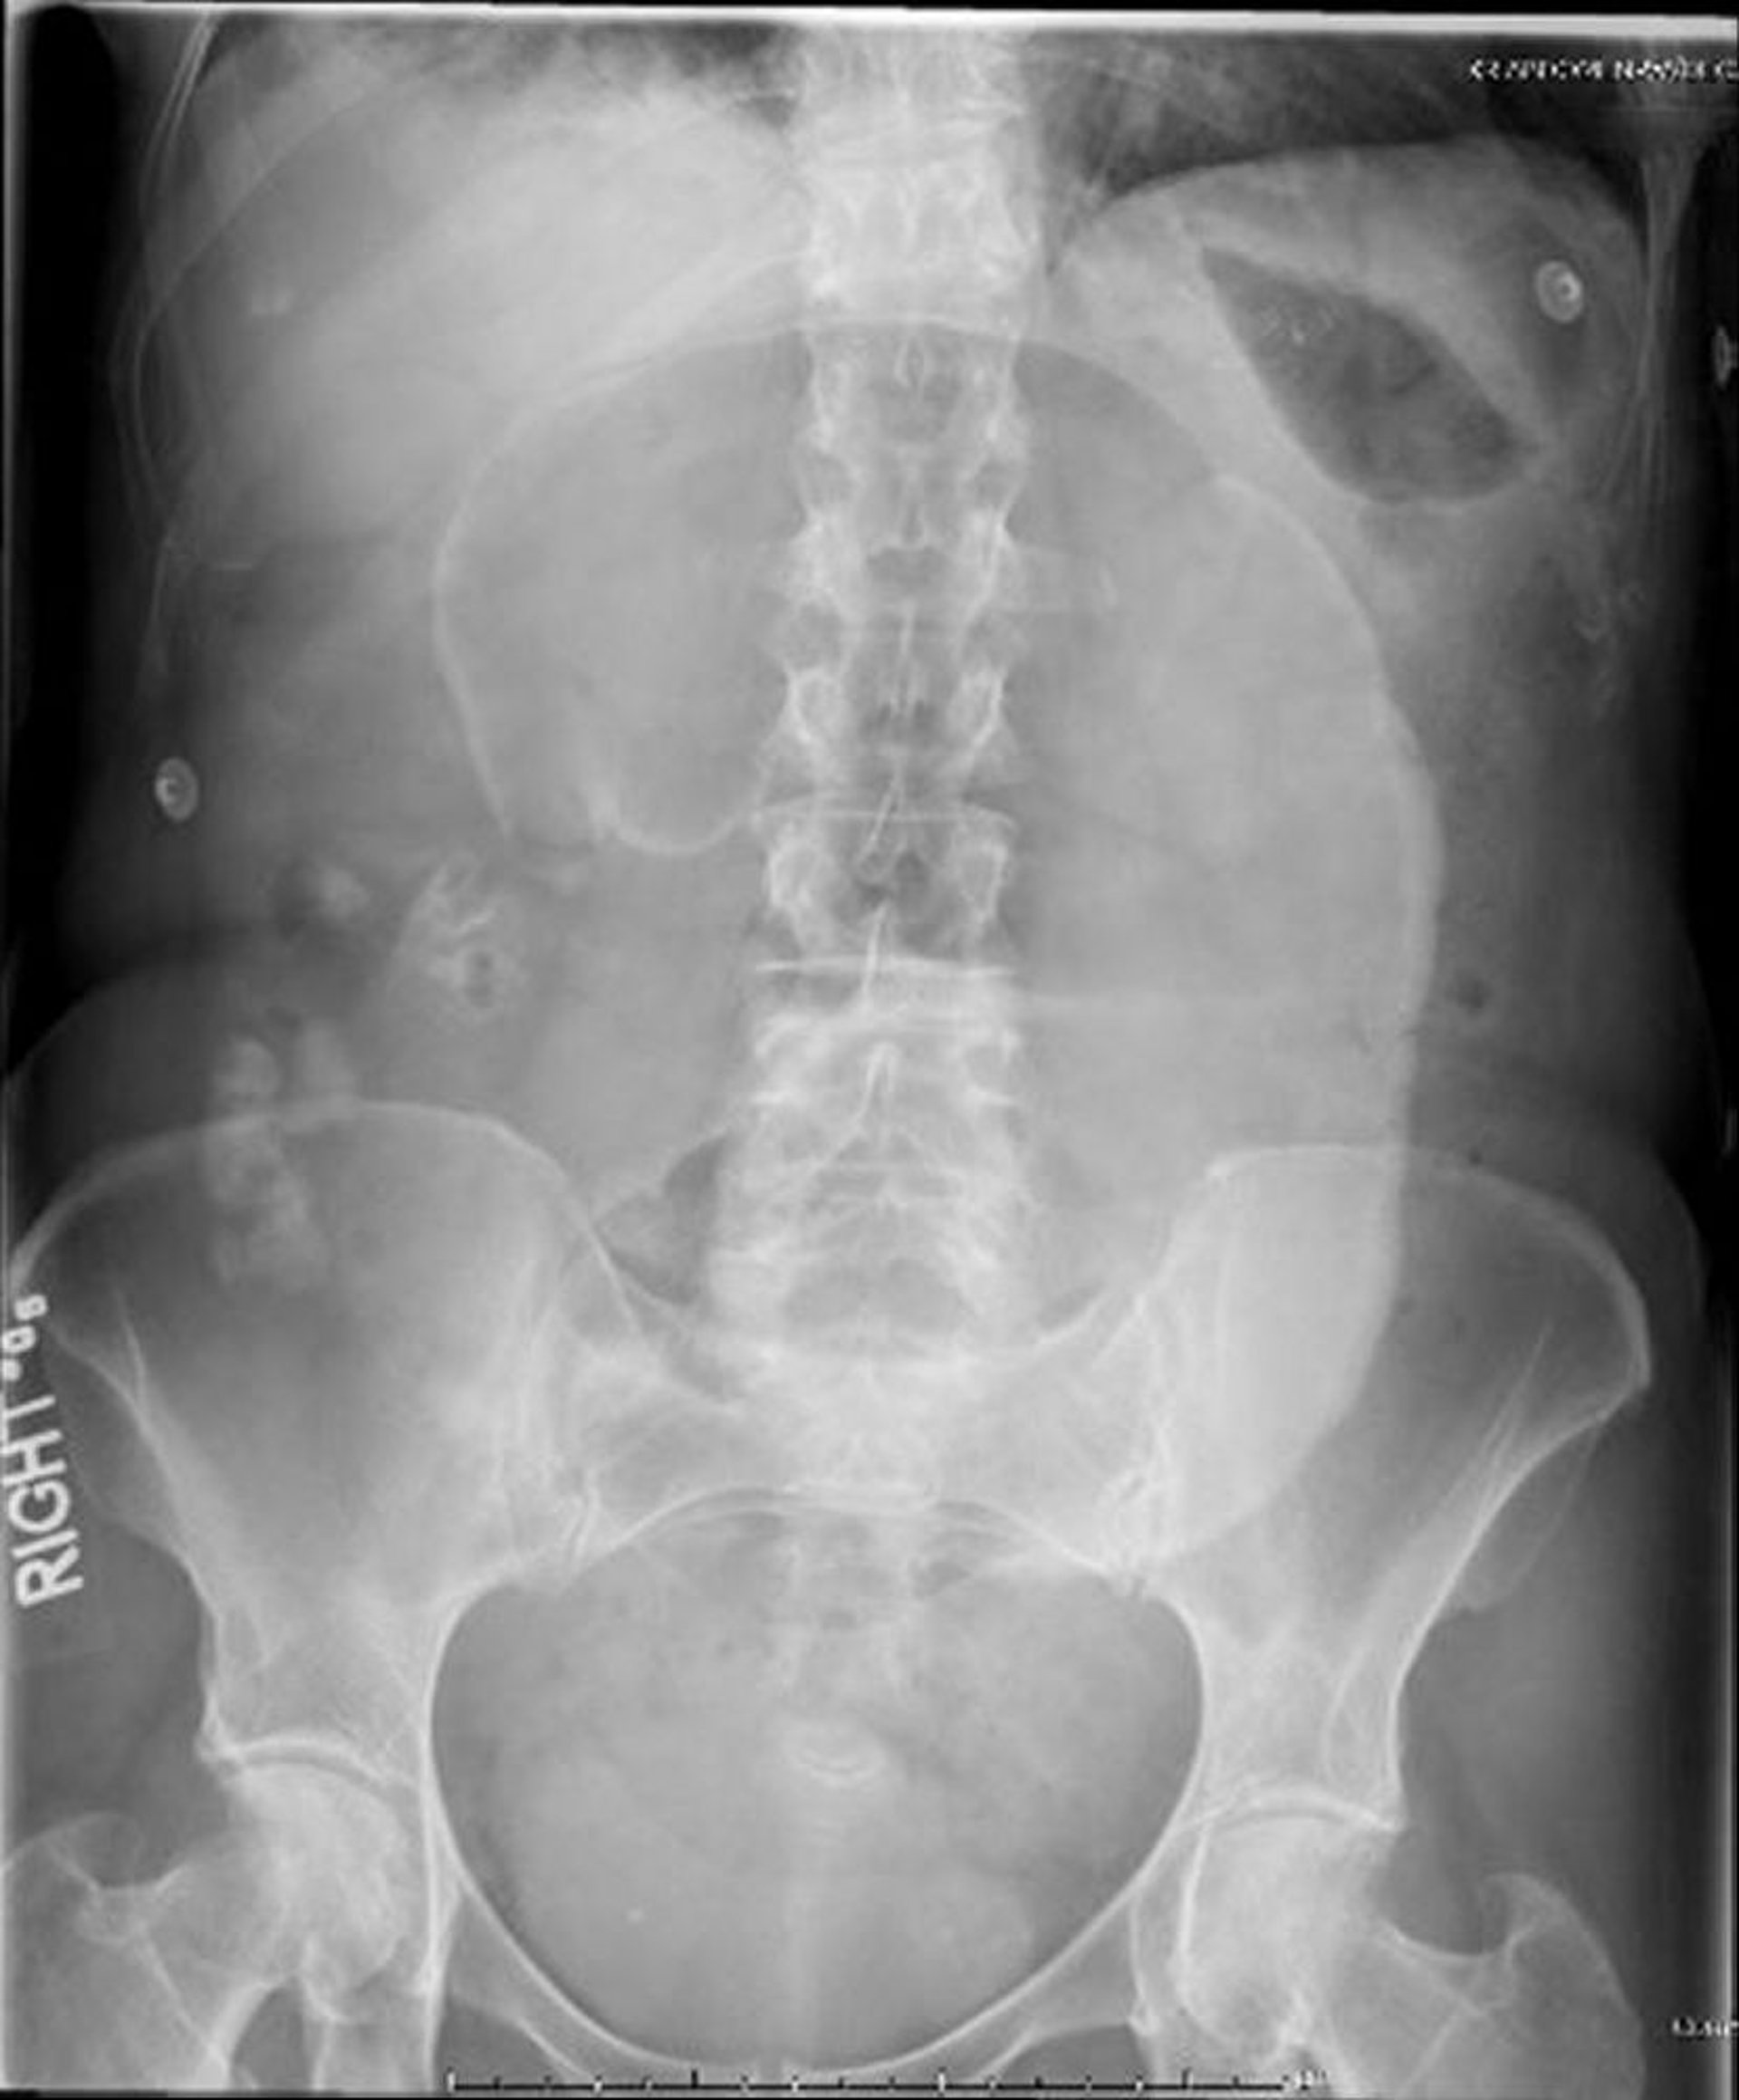

Заворот слепой кишки (рентгенография брюшной полости)

На этом рентгене брюшной полости слепая кишка закручивается вокруг брыжейки, в результате чего в проекции левого верхнего квадранта наблюдается объемное образование в виде «кофейного зерна».

Image provided by Parswa Ansari, MD.